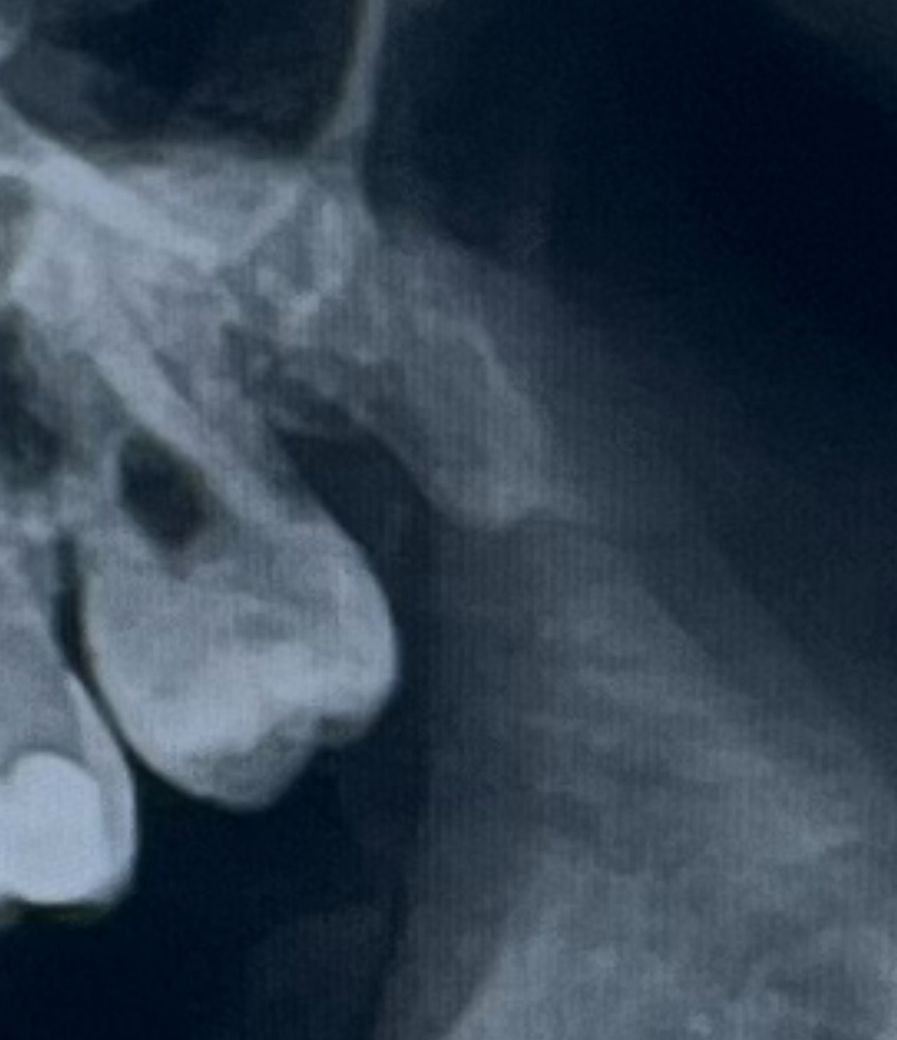

이상하게 나지도 않았고 잇몸 밖으로 나와서 잘 자랐는데 어딜가나 뽑자고 하네요 한 치과의사 선생님은 합리적으로 뽑자고 얘기를 하셨긴 했는데 정확히 기억이 안나서 올려보아요

• 1번 째 사진

사진상으로 사랑니 뒷부분이 관리가 잘안되고 잇는거 같습니다. 발치를 하시는게 좋을것같습니다.

사랑니가 특별히 문제가 없으면 꼭 빼야할 필요는 없습니다. 구강 위생 관리 상태 등을 보고 판단합니다.

사진으로 봤을 경우에는 치조골의 양이 내려간 것으로 보입니다. 하지만 치아가 불편하지 않고 흔들리지 않는다면 굳이 뽑을 필요는 없을 것으로 생각됩니다